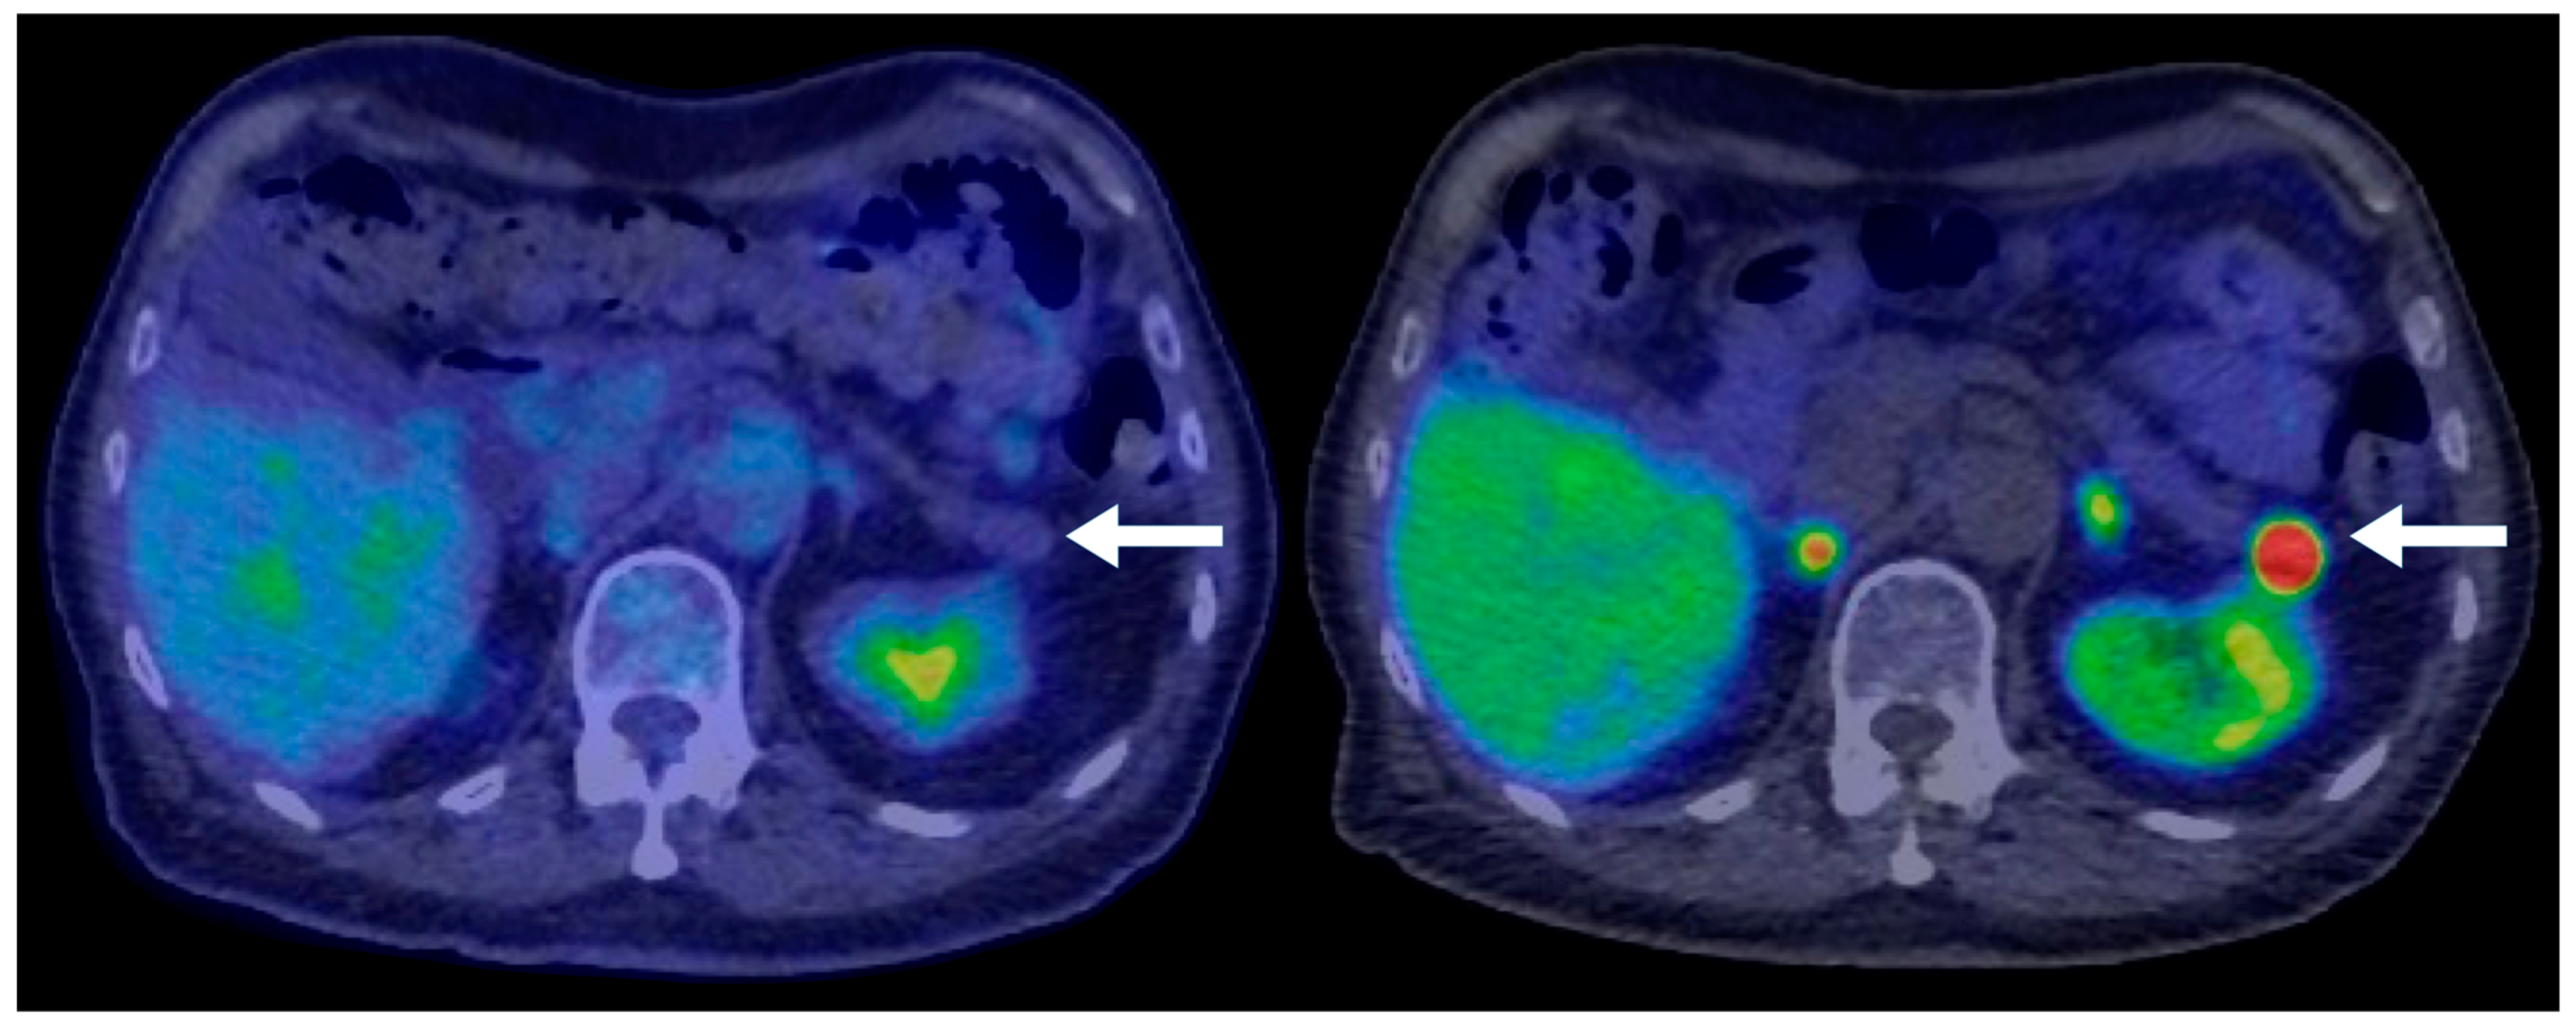

Most cases of hypoenhancing PNENs (n = 11) presented symptomatically (64%), and the lesions were significantly larger (median size 4.8 cm vs. 1.7 cm for typical PNENs). Calcifications were observed in 9% of hypoenhancing PNENs. As pointed out, these tumors were significantly more likely to present with advanced disease compared to other PNEN subtypes (Fisher’s exact test, p = 0.016) (Figure 6 and Figure 7).

Figure 6. A 47-year-old male presenting with biliary obstruction. CT (left): Arterial phase imaging shows a 2.5 cm hypodense mass in the pancreatic head (arrow). PET-CT (right): Performed after ERCP and biliary stent placement, demonstrating an intensely FDG-avid pancreatic head mass (arrow), consistent with a poorly differentiated primary neuroendocrine tumor. Metastatic disease involving porta hepatis and peripancreatic lymph nodes, as well as liver metastases, is also evident on the PET.